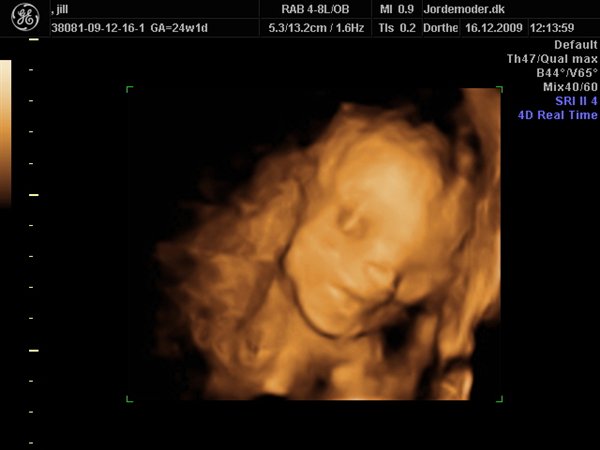

Da jeg snakkede med hende i dag sagde hun at fra uge 27 til og med uge 31 var det bedste tidspunkt at få det gjort....

Vi skal give 1400 kr for 45 minutters total gennem scanning, hvor hun fortæller, undersøger babyen fra top til tå, laver vægtskøn også får vi billeder og dvd med hjem.... Og ja det er da mange penge, men min forlovede har haft en masse vikar timer den her mdr, også sagde han at han syntes vi skulle bruge de penge på noget vi normalt ikke ville have gjort. Han sagde egentlig at jeg kunne gå ud og shoppe for dem, men jeg har termin om ti uger, så gider ærlig talt ikke bruge penge på nyt graviditets tøj, så hellere det her som vi egentlig havde valgt fra pga prisen, men som vi begge to rigtig gerne vil....